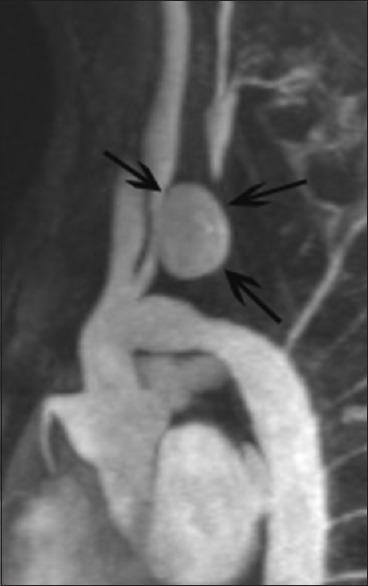

An adolescent patient with a previous history of surgical repair for interrupted aortic arch type B presented with an asymptomatic, saccular pseudoaneurysm of the proximal, common left carotid artery, identified on a follow-up magnetic resonance angiography of the thoracic large vessels. The pseudoaneurysm was successfully excluded with a covered stent. Clinical and radiological follow-up after 2 years was uneventful.

一名曾因B型主动脉弓中断接受手术修复的青少年患者,在胸部大血管的随访磁共振血管造影中发现左颈总动脉近端有无症状的囊状假性动脉瘤。该假性动脉瘤通过覆膜支架成功排除。2年后的临床和影像学随访均无异常。